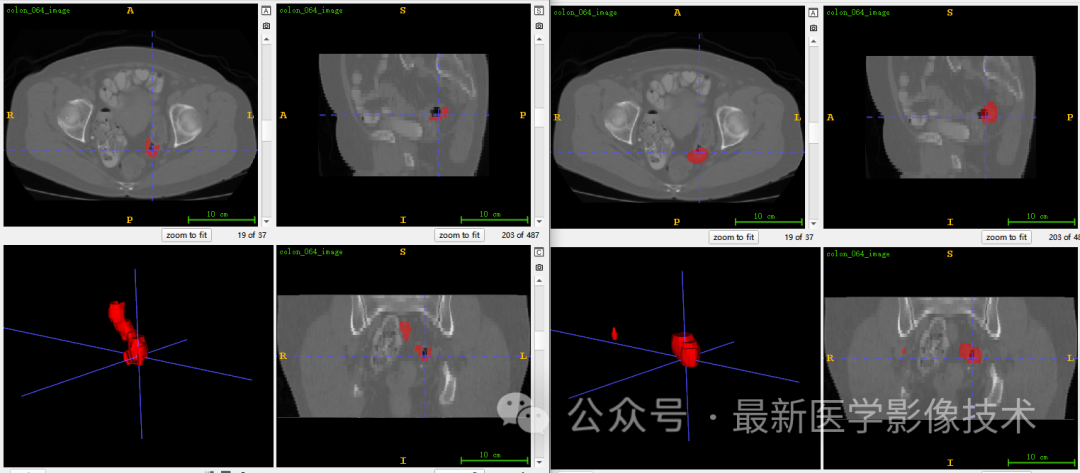

5、验证集分割结果

左图是金标准结果,右图是预测结果。